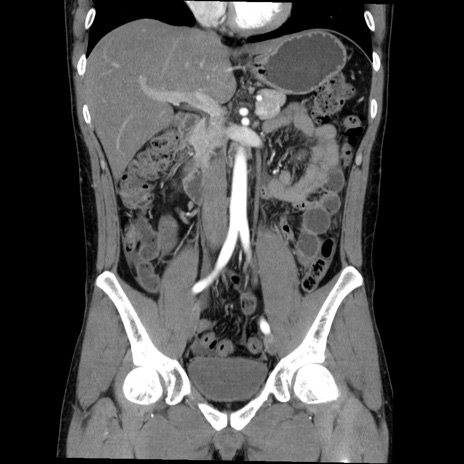

症例36(冠状断像)

【症例】20歳代 男性

【主訴】心窩部痛

【現病歴】今朝より上腹部痛あり。一旦軽快していたが再度出現したため救急要請。昨日夕に白身の魚を含む刺身を食べた。

【身体所見】BP 136/89mmHg、HR 74/min、BT 37.0℃、腹部:膨満、軟、心窩部に圧痛あり。反跳痛なし、筋性防御なし、腸雑音やや亢進あり。

【データ】WBC 17700、CRP 0.48